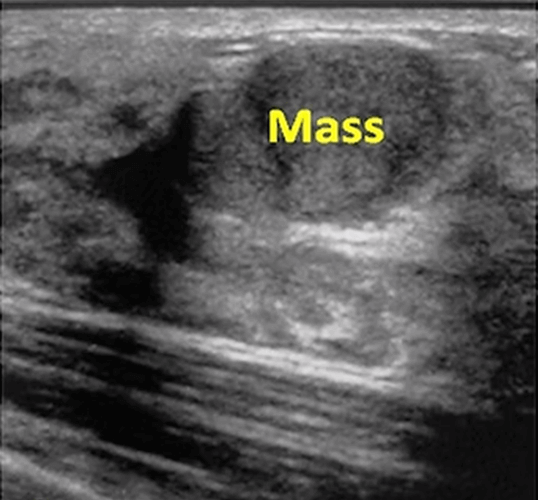

Breast cancer can be felt in the form of a mass during self-examination by the person or the doctor. Or, it can give other symptoms like breast thickening, stiffness, deformity, nipple retraction, bloody discharge. In such cases, ultrasound and mammography examinations are usually performed to determine if there is a suspicious mass in the breast. But sometimes, there is no complaint in the patient, and ultrasound and mammographies performed during routine controls may show a suspicious mass in the breast.

Ultrasound and mammography are the classical examination methods in the breast. Ultrasound is a cheap, practical and harmless (no radiation) method and it is the most commonly used examination in women under the age of 40 years. In mammography, the patient receives a small amount of radiation, but it is an indispensable diagnostic method especially for women over 40 years of age. Mammography shows cancer much clearly in breasts with a lot of fat. It cannot show cancer very well if the breast contains little fat and more fibroglandular tissue (dense breast)  which is more common in young women. In such dense breasts, one out of two cancers may be overlooked if only mammography is performed.

Ultrasound and mammography show different tumor structures better. For example, ultrasound shows the cystic masses in which the fluid is collected, and these masses are very well distinguished from solid ones.On the other hand, mammography demonstrates calcification areas better, which are hardly seen on ultrasound. Due to these complementary features, ultrasound and mammography are usually used together in the evaluation of breast masses. When mammography and ultrasound are used together, it is possible to determine 75-80% of all breast cancers.

Trucut (core) biopsy is the most commonly used biopsy method in breast. In trucut biopsy, a few millimeters wide and 1-2 cm long strips are taken from the suspected tissue and examined in pathology. In this way, the cancer is diagnosed, the subtypes of cancer are identified and receptor + genetic studies can be done, which can guide chemotherapy. The trucut biopsy is performed most frequently under ultrasonography guidance, if the mass is not seen on ultrasound, it can be performed on mammography and if it is not seen on mammography, it can be performed under the MRI guidance.

In cryoablation, the ablation area can be seen as a black iceball on ultrasound.

3. The ablation zone (iceball) is easily seen on ultrasound and it can be made sure that the entire tumor is frozen.

For cryoablation of breast cancer, first the location of the tumor is determined on ultrasound, and then the area around the skin entrance and the tumor is numbed by local anesthesia. Subsequently, cryoprobes are placed in the tumor under ultrasound guidance. The ablation process lasts for an average of one hour. After the operation, the needles are taken out and the patient may be discharged after a few hours observation. If desired, the ablated area may be taken out by the vacuum biopsy device and is examined pathologically to make sure the tumor is completely dead. After cryoablation, radiotherapy may be given to the breast if necessary. Following  ablation, patients are examined for recurrence or metastasis at regular intervals by ultrasonography, MRI or PET-CT.